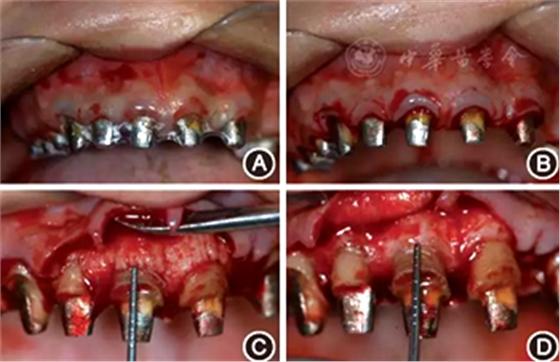

(2)手術(shù)導(dǎo)板指導(dǎo)下的牙冠延長術(shù):根據(jù)最終診斷蠟型,制作透明墊式手術(shù)導(dǎo)板(圖4B),指導(dǎo)上頜牙冠延長術(shù)(圖5),最終達到改善牙齦形、線、點的美學(xué)要求,獲得協(xié)調(diào)、對稱的美學(xué)效果。

圖5 有利于健康、功能及美學(xué)效果的牙冠延長術(shù)手術(shù)過程 A:戴入手術(shù)導(dǎo)板;B:在手術(shù)導(dǎo)板的指導(dǎo)下確定手術(shù)切口;C:翻瓣后可見唇側(cè)骨板肥厚、形態(tài)不佳,上前牙鄰面及唇側(cè)原有肩臺距離骨嵴頂≤ 2 mm,侵犯了生物學(xué)寬度;D:骨切除及骨成形后唇側(cè)骨板形態(tài),肩臺距牙槽嵴頂約4 mm;E:齦瓣復(fù)位縫合,原有肩臺均位于齦上